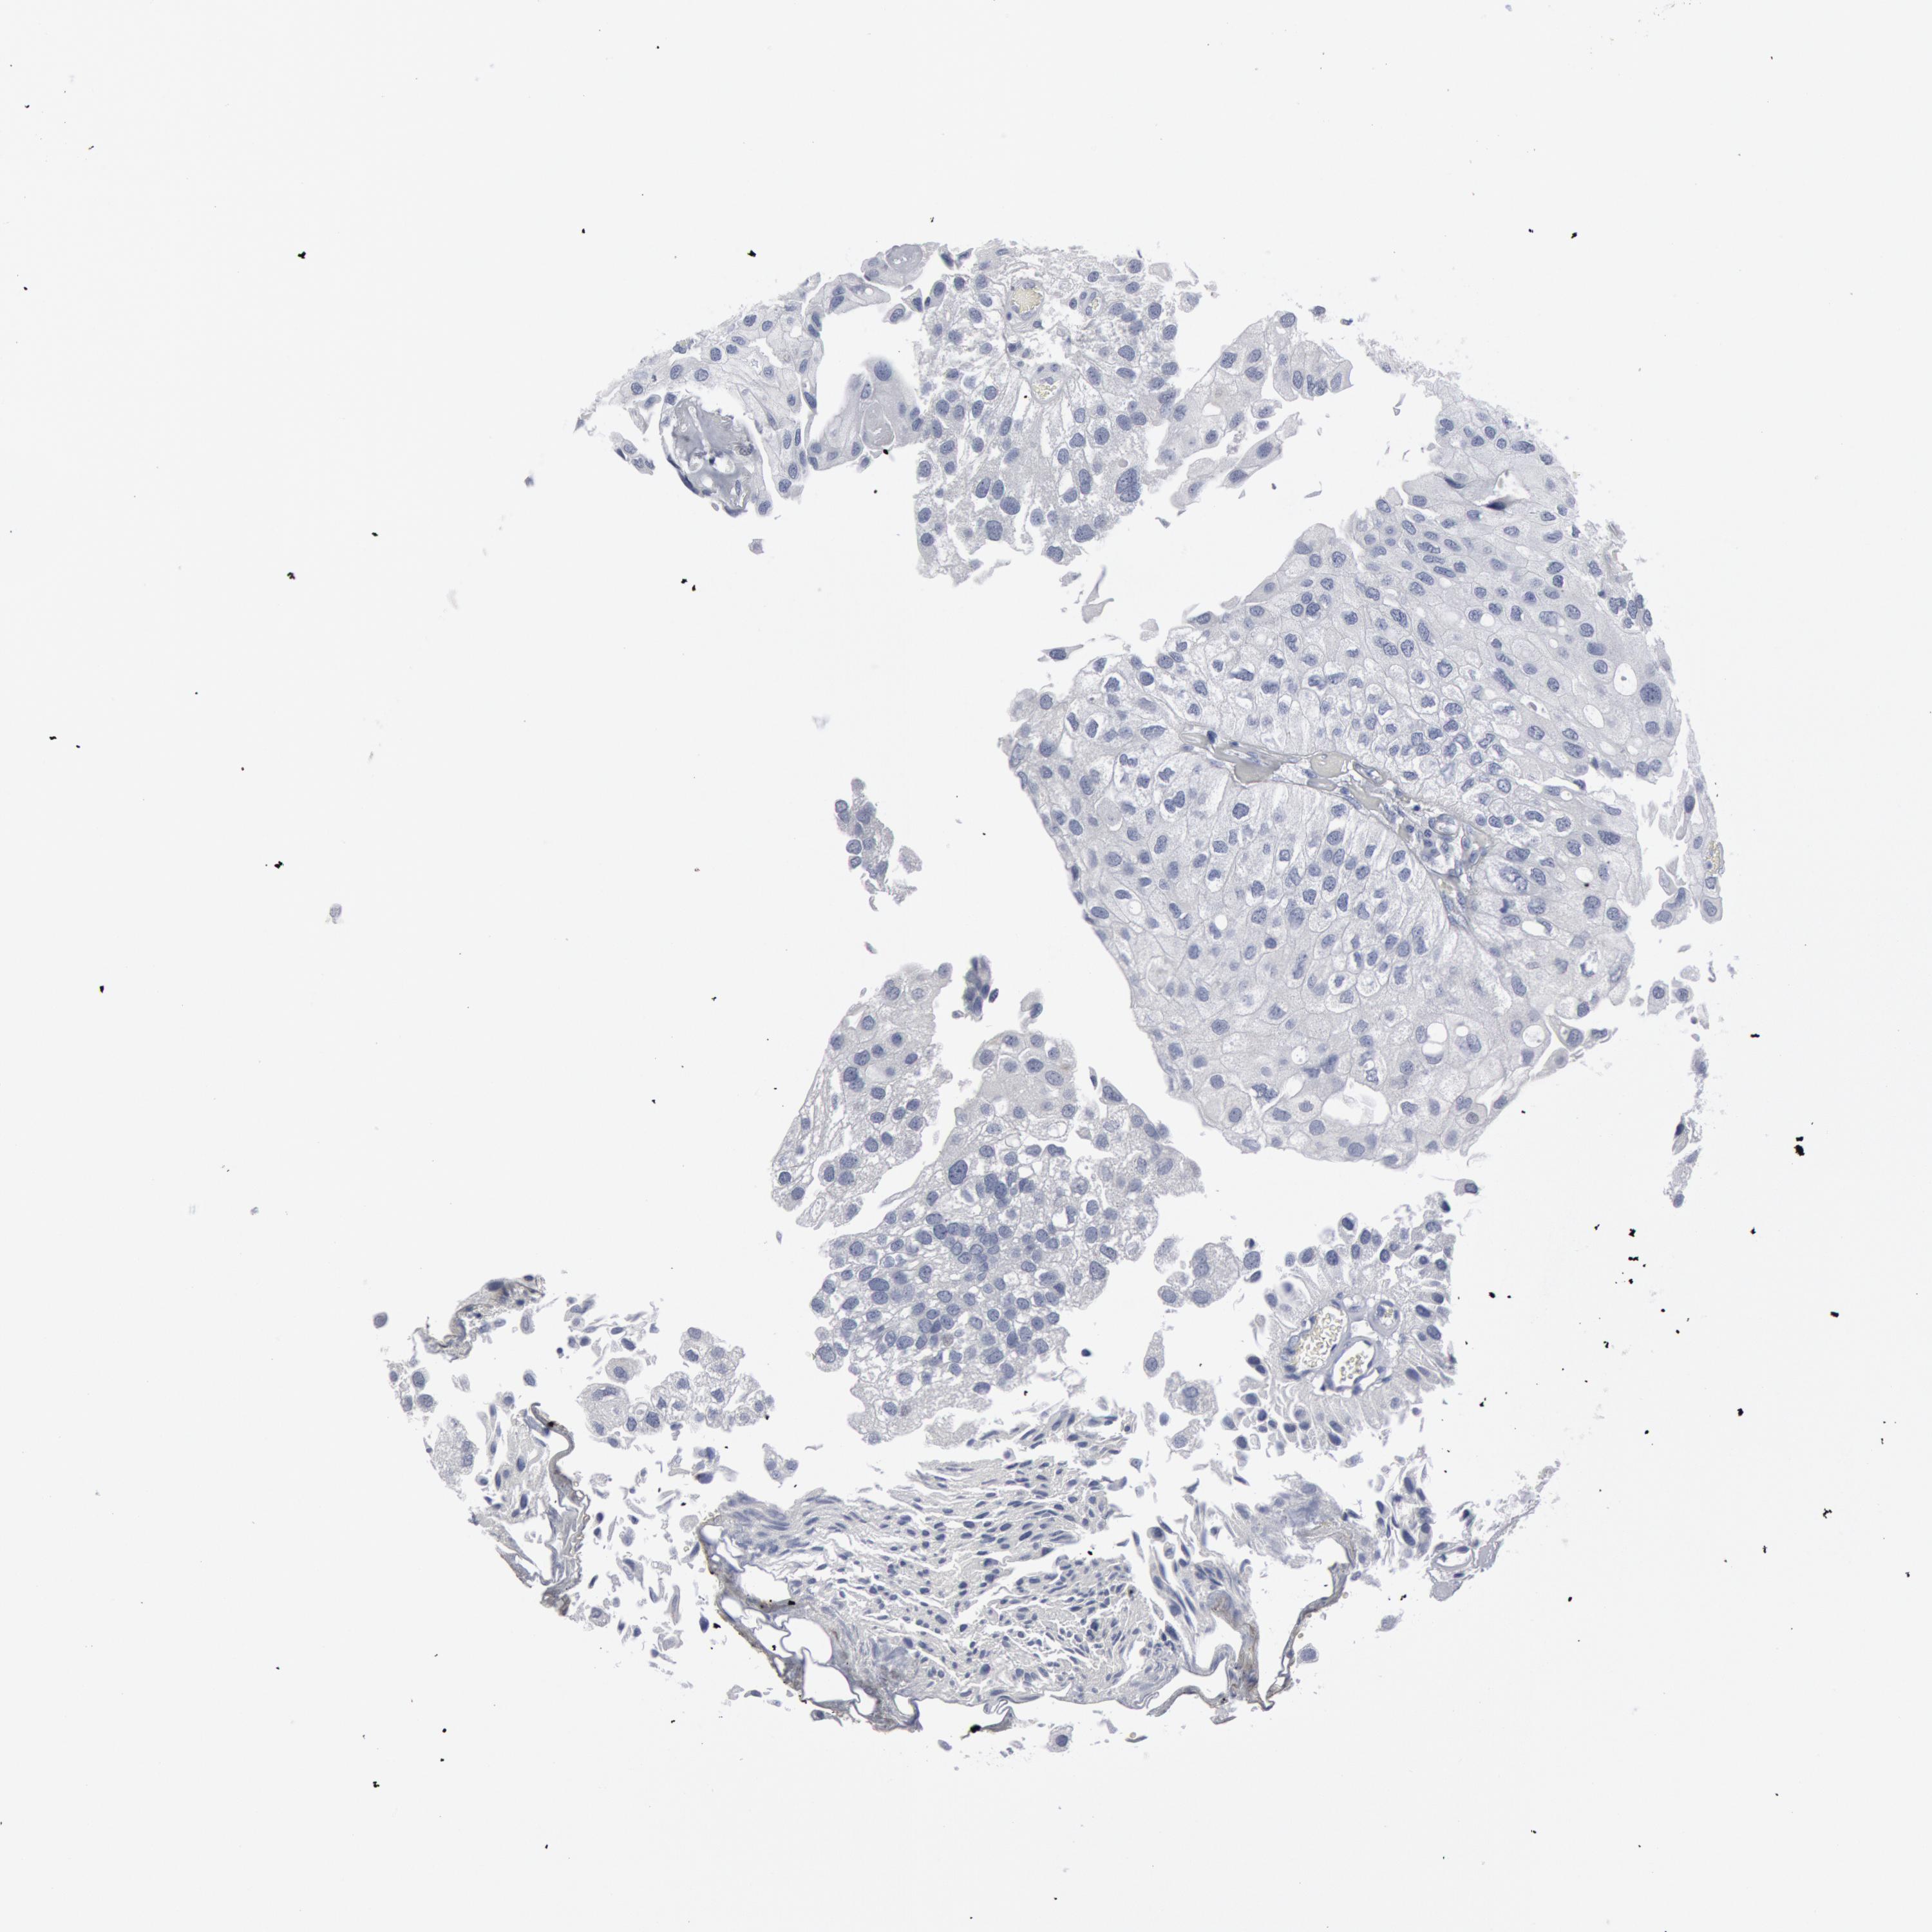

UROTHELIAL CANCER - Protein expressioni

A mouse-over function shows sample information and annotation data. Click on an image to view it in a full screen mode. Samples can be filtered based on level of antibody staining by selecting one or several of the following categories: high, medium, low and not detected. The assay and annotation is described here.

Note that samples used for immunohistochemistry by the Human Protein Atlas do not correspond to samples in the TCGA dataset.

Antibody stainingi

Antibody staining in the annotated cell types in the current human tissue is reported as not detected, low, medium, or high, based on conventional immunohistochemistry profiling in selected tissues. This score is based on the combination of the staining intensity and fraction of stained cells.

Each image is clickable and will lead to virtual microscopy that enables deeper exploration of all samples and also displays staining intensity scores, fraction scores and subcellular localization as well as patient and tissue information for each sample.

Antibody HPA001232

Antibody CAB015397

Urothelial carcinoma, High grade

Urothelial carcinoma, Low grade

Adenocarcinoma, NOS